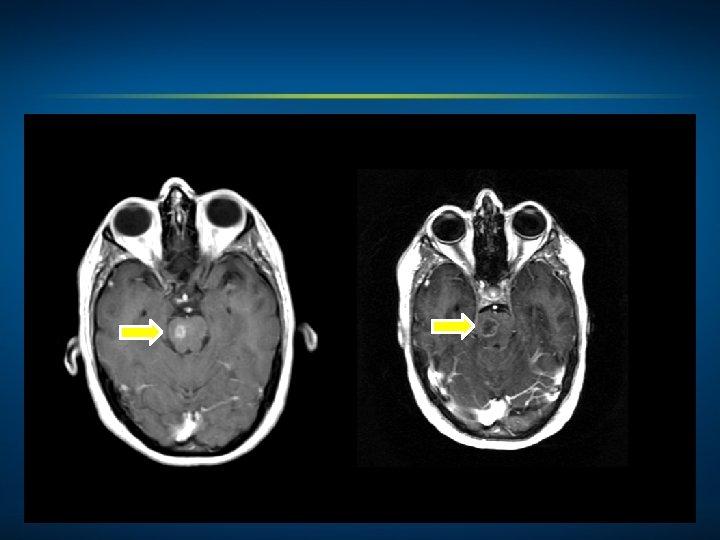

Oncology Treatment Timeline Case 4: A 52 -Year-Old Woman with Cancer of Unknown Primary and ALK-Rearranged Metastases (Ms Goodwin) WBRT Dec 2005 Carboplatin, paclitaxel and canfosfamide on clinical trial Crizotinib WBRT March 2006 April 2010 Feb 2014 Alectinib on clinical trial March 2014

4/19/2014 6/07/2014